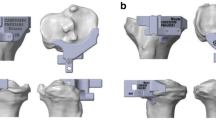

The finite element model of sclerotic bone was created according to the 3 groups of 4 types established in Part 1 and the tibial plateau and the spacer model were installed. After confirming that the 3-D model was completely free of overlapping and no deformity, HyperMesh (Altair HyperWorks, Troy, MI, USA) was used for finite-element meshing. Check the quality of finite element mesh to ensure no overlap or deformation established. Figure 3 shows the L-KA, M-MA, and S-valgus 3° finite-element models. The prosthetic stem was increased by 30 mm using the same prosthesis to simulate an extended stem prosthesis. The L-KA, M-KA, S-KA, and N-KA models were made in the same way and finite-element meshing was performed using HyperMesh software.

Bottom view of von Mises stress distribution on the contact surface of the tibial prothesis under maximum loading in each finite element model. N: none = 0 mm; S: small = 5 mm; M: medial = 10 mm; L = 15 mm; MA: mechanical alignment; KA: kinematic alignment. Left side on the figure indicates medial condyles